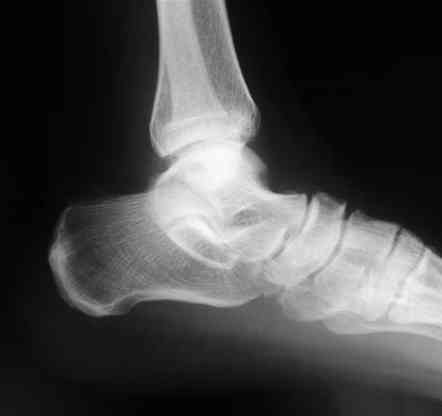

Лодыжку так ипрооперировал двумя 3.5 мм шурупами пришлось открыть - закрыто не удалось адекватно отрепонировать, при открытии - надкостничная

интерпозиция.

Я бы лодыжку зафиксировал двумя 3.5 или 4.0 мм лодыжечными шурупами, без смещения можно и закрыто, но это будеть видно во время операции.

В приложении отправляю послеопер. снимки бедра и лодыжки обсуждаемого вчера больного.

В приложении послеоперационные картинки.